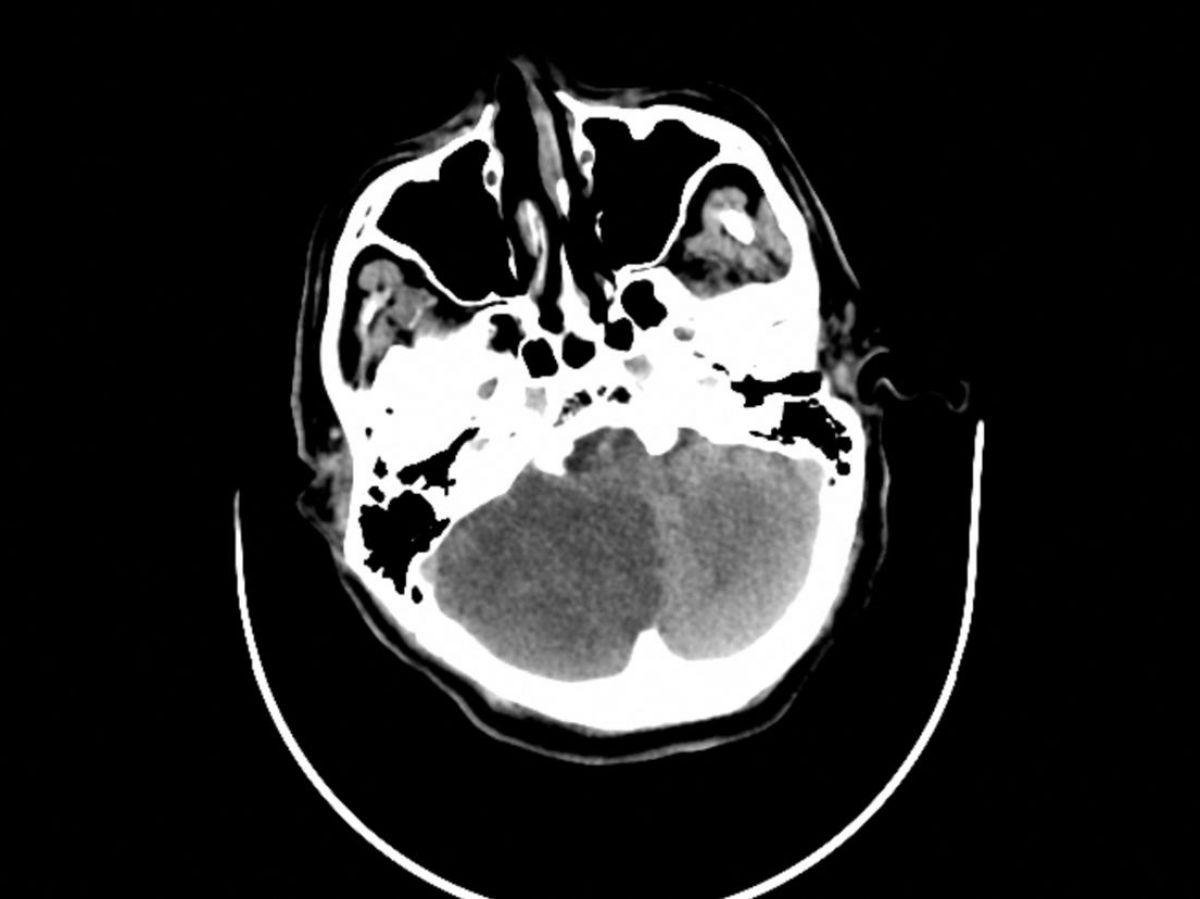

Chaque année, les AVC tuent 35.000 Français, représentant la première cause de mortalité féminine et la seconde masculine.[Lire l'article en intégralité]